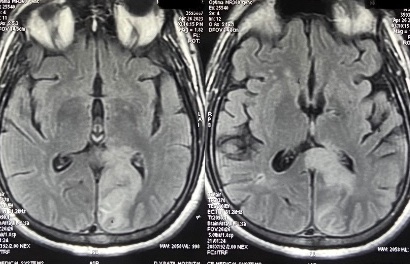

This gentleman woke up to realise he cannot read the newspaper He is able to write, but unable to read. What’s more fascinating?! He is unable to rea